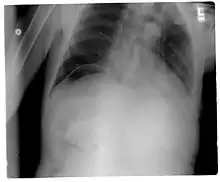

استرواح الصفاق[1] (بالإنجليزية: Pneumoperitoneum) هو وجود الهواء أو غاز في التجويف البطني (البريتواني). في الحالة الطبيعية لا يوجد غاز في تجويف البطن، ولكن انثقاب المعدة أو الأمعاء يؤدي إلى خروج الغازات إلى تجويف البطن. غالباً ما ترى على صورة الأشعة السينية (X-ray) على شكل فقاعة هواء (بالإنجليزية: Air bubble) أو هلال غازي كما يسميه الأطباء في سوريا، وهي العلامة الشعاعية التي تشير بقوة لوجود استرواح الصفاق.

![]() تصوير لمنطقة الصدر بالأشعة السينية، إن الفقاعة الهوائية تحت نصف الحجاب الأيمن (على يسار الصورة، السهم الأسود) تشير غالباً إلى استرواح الصدر. تصوير لمنطقة الصدر بالأشعة السينية، إن الفقاعة الهوائية تحت نصف الحجاب الأيمن (على يسار الصورة، السهم الأسود) تشير غالباً إلى استرواح الصدر. | |